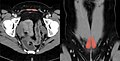

muscles of the human torso

Media in category "Muscles of the human torso"

The following 90 files are in this category, out of 90 total.